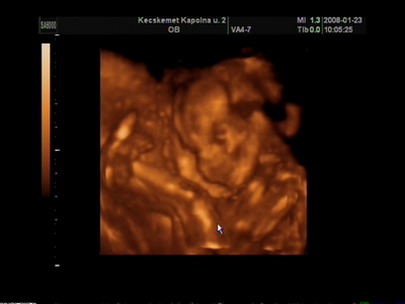

Dettus-Ma pontosan 39+4. Jól elrontottam a vonalzót!